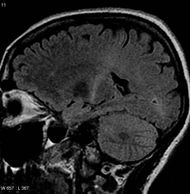

MRI (parasagittal FLAIR) demonstrates increased T2 signal within the posterior part of the internal capsule and can be tracked to the subcortical white matter of the motor cortex, outlining the corticospinal tract, consistent with the clinical diagnosis of ALS